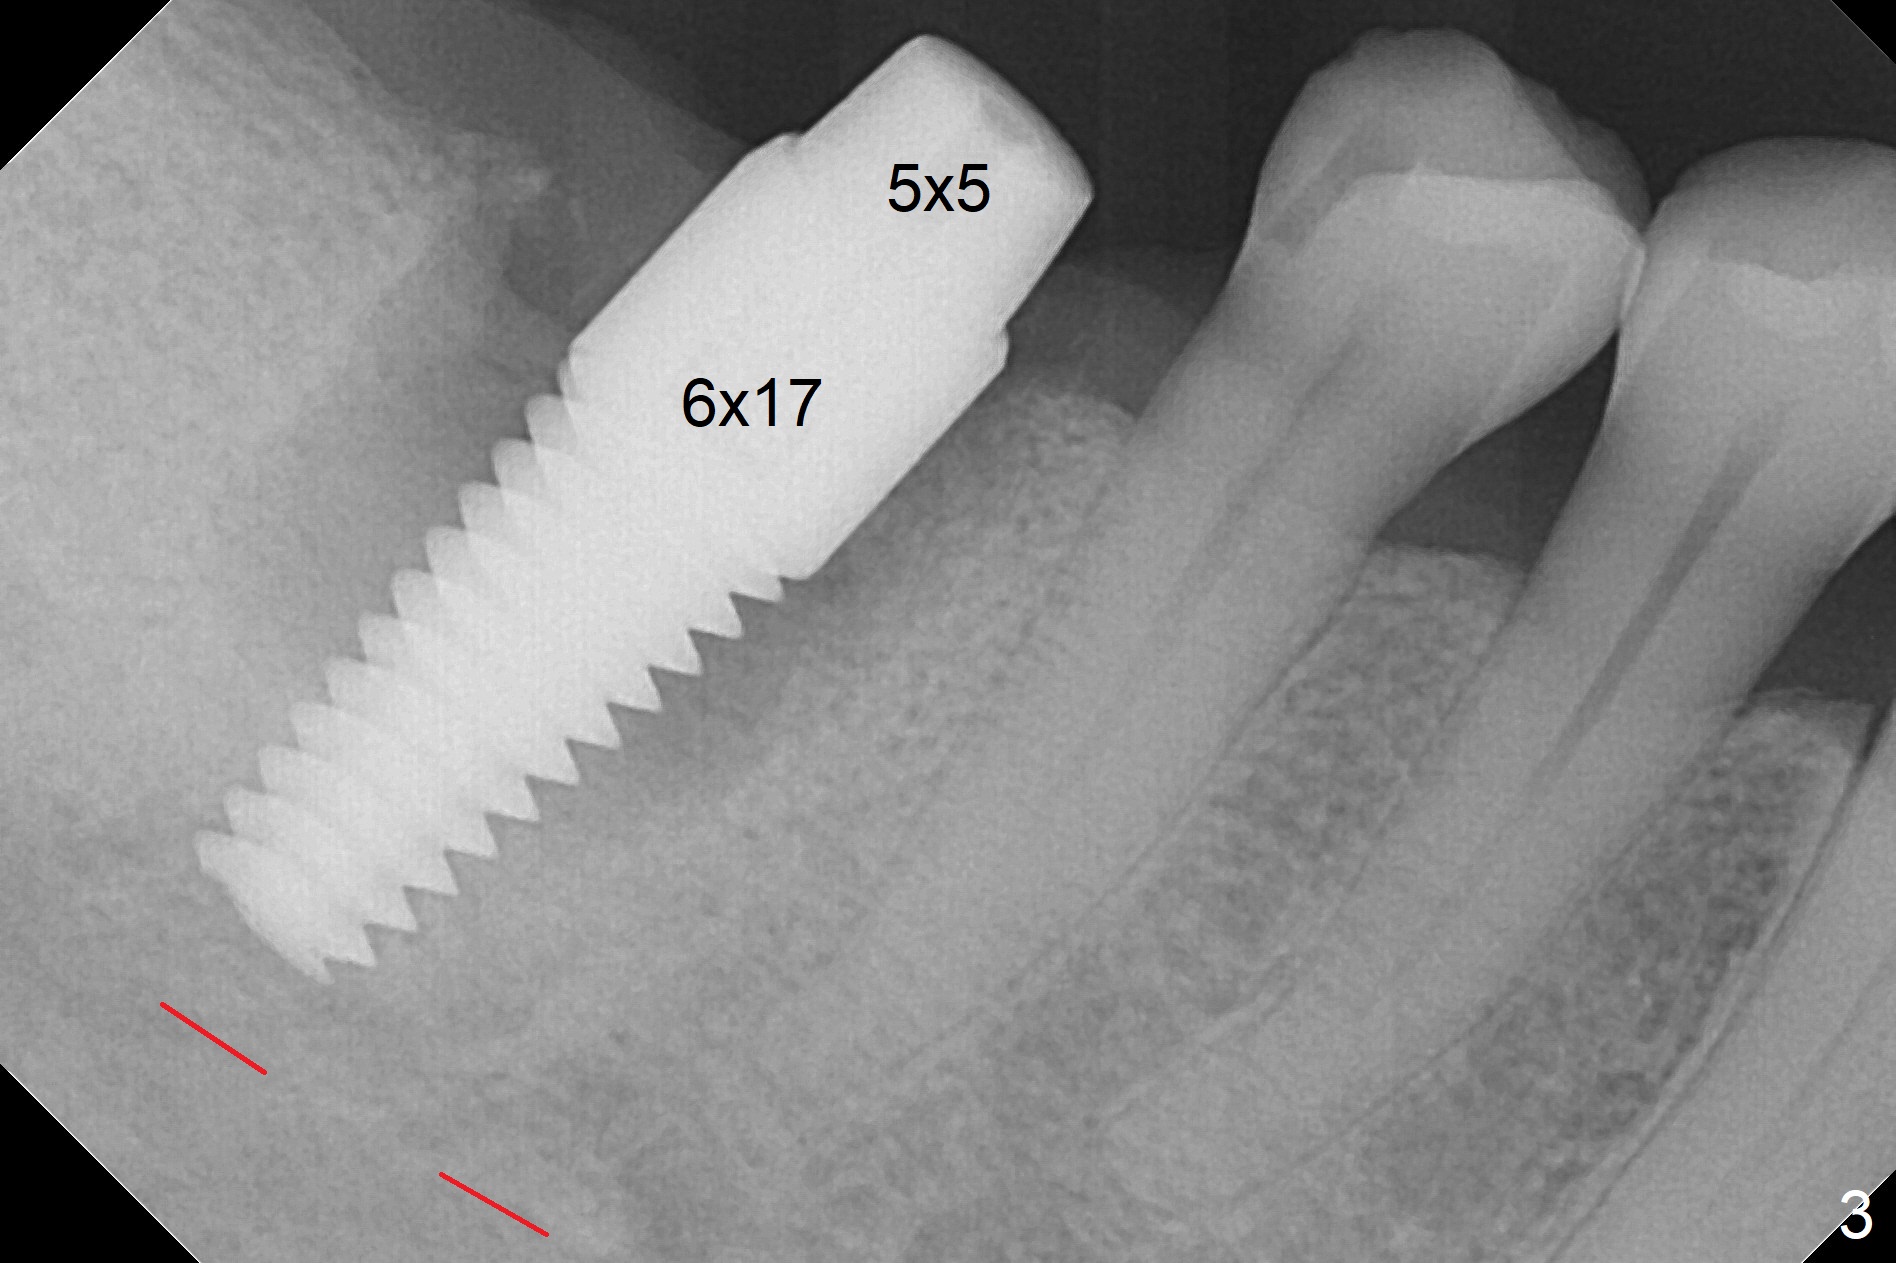

After extraction of the tooth #30 and curettage, the septum becomes so thin that the most coronal portion has to be removed with Rongeur and surgical fissure bur (bone height reduction). Initial osteotomy depth is ~ 4 mm from the flattened septum (Fig.1 (yellow dashed line: apical end of the osteotomy)). Following sequential osteotomy (with intact osteotomy wall), a 6x17 mm tap is placed with apparent clearance from the Inferior Alveolar Canal (Fig.2). When the same size implant is placed with 60 Ncm (Fig.3), the nervous patient feels that the implant is too long (causing pain). CT (Fig.4) and panoramic X-ray (Fig.5) show limited clearance (1.4 mm), but compression of the canal due to high torque could not be ruled out. Since limited amount of the native bone (4.1 mm) for primary stability, the implant is not backed up immediately. Vanilla graft is placed after fabrication of an immediate provisional (Fig.6 *). In brief, immediate implant should be avoided when the septum is thin or the native bone is less than 5 mm (3 mm for primary stability; 2 mm for clearance). In fact the implant has to be untorqued 4-5 times of turn to relieve pain nearly 1 month postop. The patient returns for impression 5 months postop (4 months post implant back up, Fig.7). When the abutment is changed to 5x5 mm and prepared, she reports earache (residual nerve damage?). The patient has had the similar complaint 9 months postop; it appears that there is radiolucency distally (Fig.8 >, as compared to radiopaque mesially (*)). The distal gingiva is tender. With a remade permanent crown, oral hygiene instruction is provided. If necessary, CBCT is taken with possible bone graft.